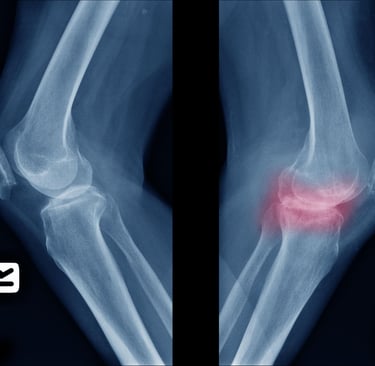

For starters, we must know what osteoarthritis is – it occurs when the protective cartilage in the joints gradually breaks down. Cartilage acts like a shock absorber, allowing bones to glide smoothly during movement. When it wears away you may feel bones starting to rub against each other, swelling of the knees and lastly joint movement becomes painful even becoming stiff. The joints that are commonly affected are the weight-bearing such as knees, hips, hands and spine. According to the World Health Organization, osteoarthritis affects over 528million individuals globally!

Many patients ignore the early symptoms. However, recognizing them early helps prevent worsening joint damage. Typical early symptoms include joint pain or after movement, morning stiffness lasting less than 30 minutes, joint tenderness when pressing the area, reduced flexibility and difficulty bending the joints, a grinding sensation when moving the joint (crepitation) and bone spurs that feel like hard lumps around the joint. In my clinic, the knee joint is the most frequently affected area.